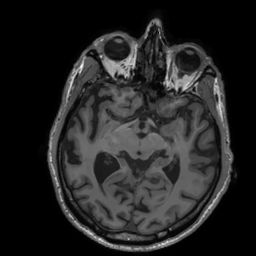

Multi-modality (or multi-channel) imaging is becoming increasingly important and more widely available, e.g. hyperspectral imaging in remote sensing, spectral CT in material sciences as well as multi-contrast MRI and PET-MR in medicine. Research in the last decades resulted in a plethora of mathematical methods to combine data from several modalities. State-of-the-art methods, often formulated as variational regularization, have shown to significantly improve image reconstruction both quantitatively and qualitatively. Almost all of these models rely on the assumption that the modalities are perfectly registered, which is not the case in most real world applications. We propose a variational framework which jointly performs reconstruction and registration, thereby overcoming this hurdle. Numerical results on simulated and real data show the potential of the proposed strategy for various applications in multi-contrast MRI, PET-MR, and hyperspectral imaging: typical misalignments between modalities such as rotations, translations, zooms can be effectively corrected during the reconstruction process. Therefore the proposed framework allows the robust exploitation of shared information across multiple modalities under real conditions.